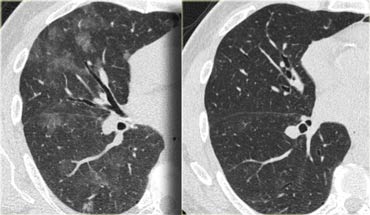

那么,哪些磨玻璃结节可能会自行消失呢?具备以下特征的结节通常有较大可能性自行消失:结节未成形,与周围组织边界不清晰,更像是炎症反应,CT值偏低,密度散在,没有明显的实质性成分。此外,近期出现感冒、发烧、发水痘或肺部感染的患者也可能出现磨玻璃结节。因此,如果最近患有感冒、发热或肺部感染,最好避免进行CT检查。